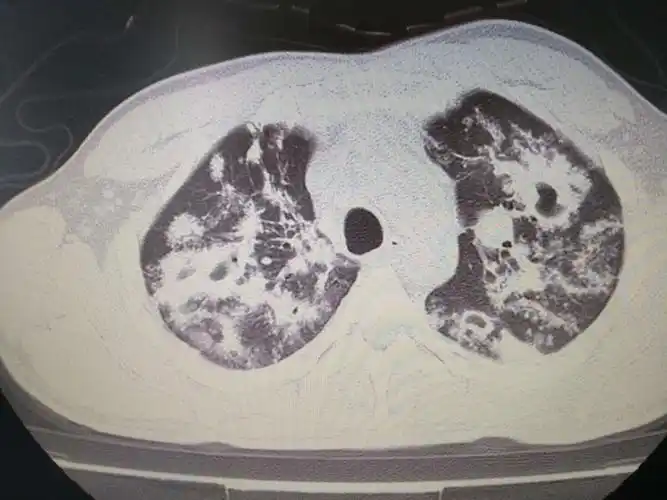

重症肺炎,肺结核